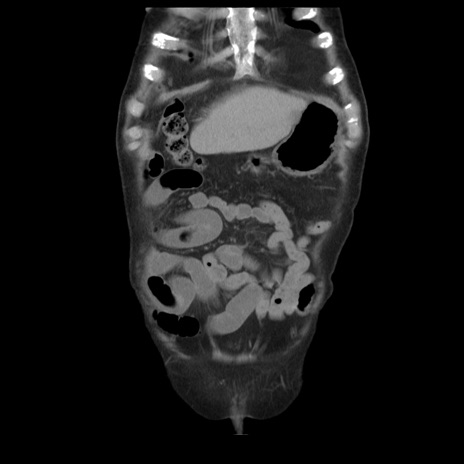

症例21(冠状断像)

【症例】70歳代男性

【主訴】腹痛

【現病歴】肝硬変・肝細胞癌にてかかりつけの方。約9時間前に食後より腹痛出現。症状が徐々に増悪し、嘔吐出現したため来院。

【既往歴】肝硬変、肝細胞癌(RFA、TACE後)

【身体所見】意識清明、表情苦悶様、BT 36℃、BP 129/78mmHg、P 88bpm、SpO2 97%(RA)、右上腹部から心窩部にかけて圧痛あり、反跳痛なし、筋性防御あり。

【データ】WBC 5800、CRP 0.16